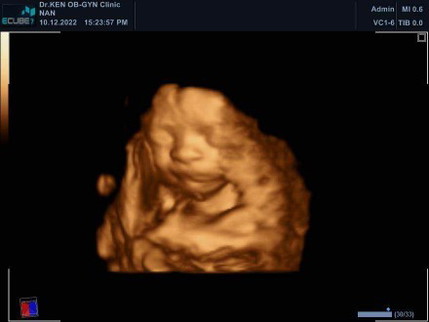

ทีมมีนาคม ก่อนท้อง39 บัจจุบัน47.3 ท้อง27วีค3วัน น้ำหนักน้อง953กรัม เพศชาย ขี้อายคับกว่าจะยอมเปิดหน้า

เห็นหน้าชัดมากเลยคะแม่

เห็นหน้าชัดเลยค่ะ

ปกติฝากรัฐบาลค่ะแม่ แต่หมอซาวให้ไม่ชัดเจนเลยไปซาว4มิติ คลีนิคข้างนอกค่ะ น้องขี้อายมากๆหมอปลุกเเล้วปลุกอีก ไม่ยอมเอามือออก บังหน้าเอาไว้ ยอมเปิด3วิเอง555+

กว่าจะยอมเปิดหน้าให้เห็น น้องเอามือบังหน้าไว้ค่ะแม่